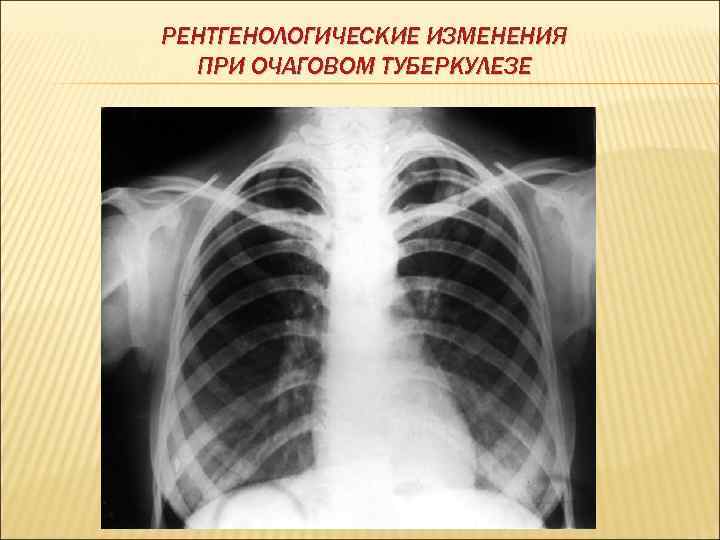

ОЧАГОВЫЙ ТУБЕРКУЛЕЗ Клиническая форма туберкулеза, которая характеризуется наличием различных по генезу и давности небольших (до 10 мм в диаметре, преимущественно продуктивного характера), очагов в пределах 1 -2 сегментов в одном или обоих легких и малосимптомным течением. Выделяют: Мягкоочаговый туберкулез– это очаговый туберкулез в фазе инфильтрации, то есть свежая форма заболевания, которую необходимо лечить. Фиброзно-очаговый туберкулез – это очаговый туберкулез в фазе уплотнения и обызвествления. Эта форма развивается в результате инволютивного течения любой клинической форсы туберкулеза, чаще инфильтративной, диссеминированной.

РЕНТГЕНОЛОГИЧЕСКИЕ ИЗМЕНЕНИЯ ПРИ ОЧАГОВОМ ТУБЕРКУЛЕЗЕ

КЛИНИЧЕСКАЯ КАРТИНА Большинство больных очаговым туберкулезом не отмечают никаких симптомов заболевания. Вместе с тем, при очаговом туберкулезе могут наблюдаться симптомы интоксикации и симптомы поражения органов дыхания. Интоксикационный синдром проявляется длительным субфебрилитетом, снижением аппетита и трудоспособности, потливостью, недомоганием. Симптомы поражения органов дыхания проявляются в виде жалоб больного на покашливание с незначительным выделением мокроты.